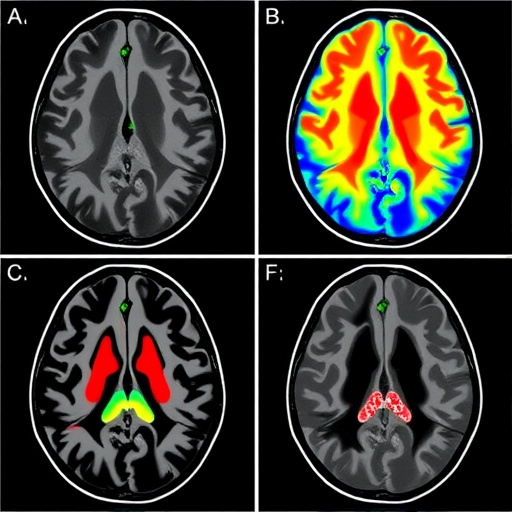

The team employed state-of-the-art phase-contrast MRI protocols, specifically optimized to capture subtle fluid velocities within the cranial cavity. These methods enable a pixel-by-pixel quantification of flow velocities, capturing oscillations synchronous with cardiac activity. This is crucial because heart-driven pulsations are understood to be major contributors to CSF movement, but the regional heterogeneity of their effect had remained elusive until now.

Focusing on a cohort of healthy volunteers, the investigators mapped CSF flow at multiple brain loci, including ventricular spaces, the subarachnoid compartments, and perivascular regions. Their quantitative data revealed that certain compartments exhibit pronounced flow signatures corresponding to cardiac and respiratory cycles, whereas others showed dampened or delayed responses. This spatiotemporal coupling between vascular rhythms and CSF movement offers compelling evidence for localized biomechanical interactions modulating fluid transport.

Critically, the study’s methodology addresses previous technical hurdles by combining advanced MR data acquisition with sophisticated modeling frameworks that account for pulsatile flow and tissue compliance. By tailoring imaging sequences to the temporal characteristics of cardiac-induced flow, the researchers maximized sensitivity to subtle velocity changes that were otherwise obscured in conventional scans. Moreover, the rigorous validation against physiological parameters adds robustness to the findings.

The technological advancements driving this work are equally notable. Employing phase-contrast MRI as a non-invasive probe of brain fluid movement with such granularity requires both hardware precision and computational finesse. The integration of time-resolved imaging with cardiac gating techniques exemplifies the cutting edge of neuroimaging innovation, merging engineering and clinical insight to tackle longstanding neuroscientific questions.